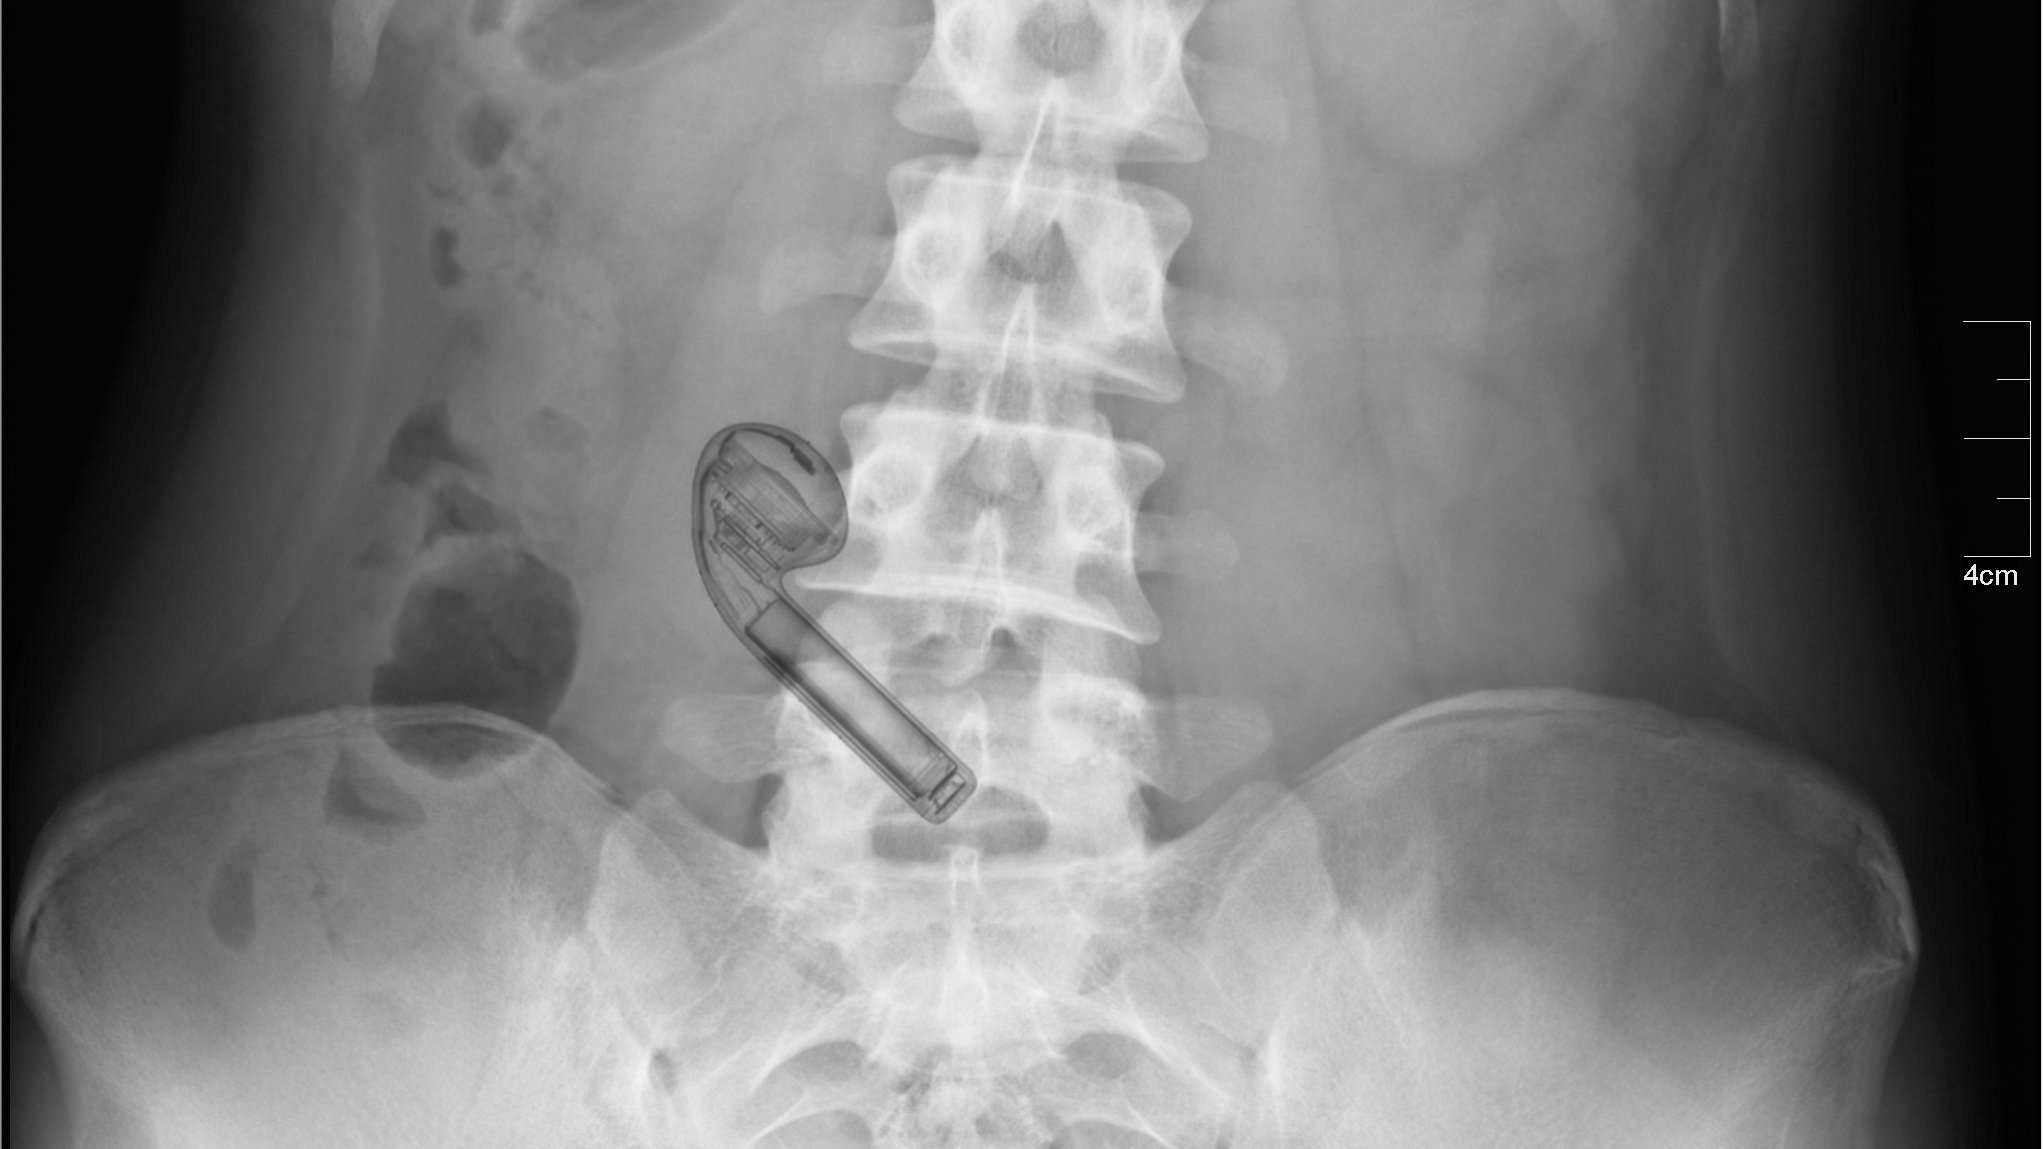

An X-ray image taken at Children's Healthcare of Atlanta, Georgia displayed the device resting peacefully inside the boy's stomach, reports WSB-TV.

X-rays showed the wireless headphone was still intact inside the body.